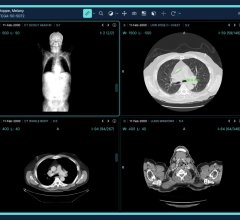

The conferencing system used in Hammersmith combined MultiSense's telemedicine infrastructure with Barco's surgical display technology. The system provided viewers with a real-time, two-way communication link between the operating theater and the conference room, thereby enabling detailed discussions while the procedure was being performed. Thanks to the surgical display's intelligent picture-in-picture functionality, the audience had a high-definition view of the operation on screen, including local and remote camera images, the patient's vital signs, and the endoscopic video of the operation.

“The MultiSense medical cart provides a very efficient and comfortable way of visualizing and sharing images and data, both inside and outside of the surgery suite,” said Dr. Punjabi. “The most important aspect of the solution, however, is the excellent quality of the patient images. The Barco MDSC-2124 surgical display guarantees excellent performance under high ambient light conditions, and allows for detailed discussion during the procedure. Moreover, at 1,920 x 1,200, its high-definition resolution improves depth perception, enhances hand-view coordination and allows for better patient care overall.”